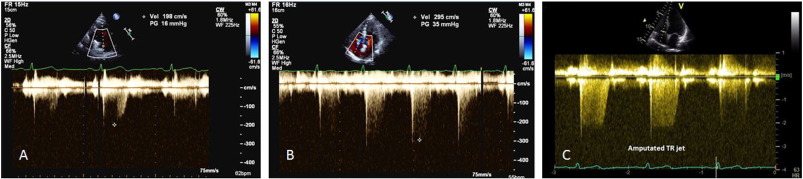

A lesser degree of TR may occur in a compensated right ventricle (due to elevated ventricular pressure) and this could lead to underestimation of PASP. Similarly, severe TR could cause equalisation of right atrial and ventricular pressures which may cause the TR Doppler envelope to be cut short, leading to underestimation of PASP (Fig. 2 -C) [8] . RAP is often overestimated if IVC measurement is used, leading to overestimation of PASP [10] . Calculations using the TR trace assume that there is no pulmonary valve stenosis and may be inaccurate in the presence of RV systolic dysfunction. TR signal could be poor in a good proportion of patients with lung disease, and TRmax measurement should be avoided in the absence of a good Doppler envelope (Fig. 2 ) [11] .

|

Fig. 2. Pitfalls in TR peak measurement. A, B—Peak TR measurement with incomplete trace could lead to underestimation. C—Amputated jet could occur in severe TR that could lead to underestimation. |